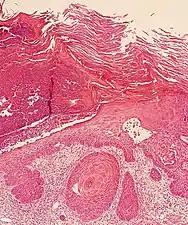

In invasive cSCC, tumor cells infiltrate through the basement membrane. The infiltrate can be somewhat difficult to detect in the early stages of invasion: however, additional indicators such as full thickness epidermal atypia and the involvement of hair follicles can be used to facilitate the diagnosis. Later stages of invasion are characterized by the formation of nests of atypical tumor cells in the dermis, often with a corresponding inflammatory infiltrate.[12]

Superficially invasive cutaneous squamous-cell carcinoma. These lesions often do not show the marked pleomorphism and atypical nuclei of cSCC in situ, but manifest early keratinocyte invasion of the dermis.[12]

High magnification demonstrates the pleomorphism of the invading keratinocytes[12]

Invasive nests with characteristic large celled centers. Ulceration (at left) is common in invasive cSCC.